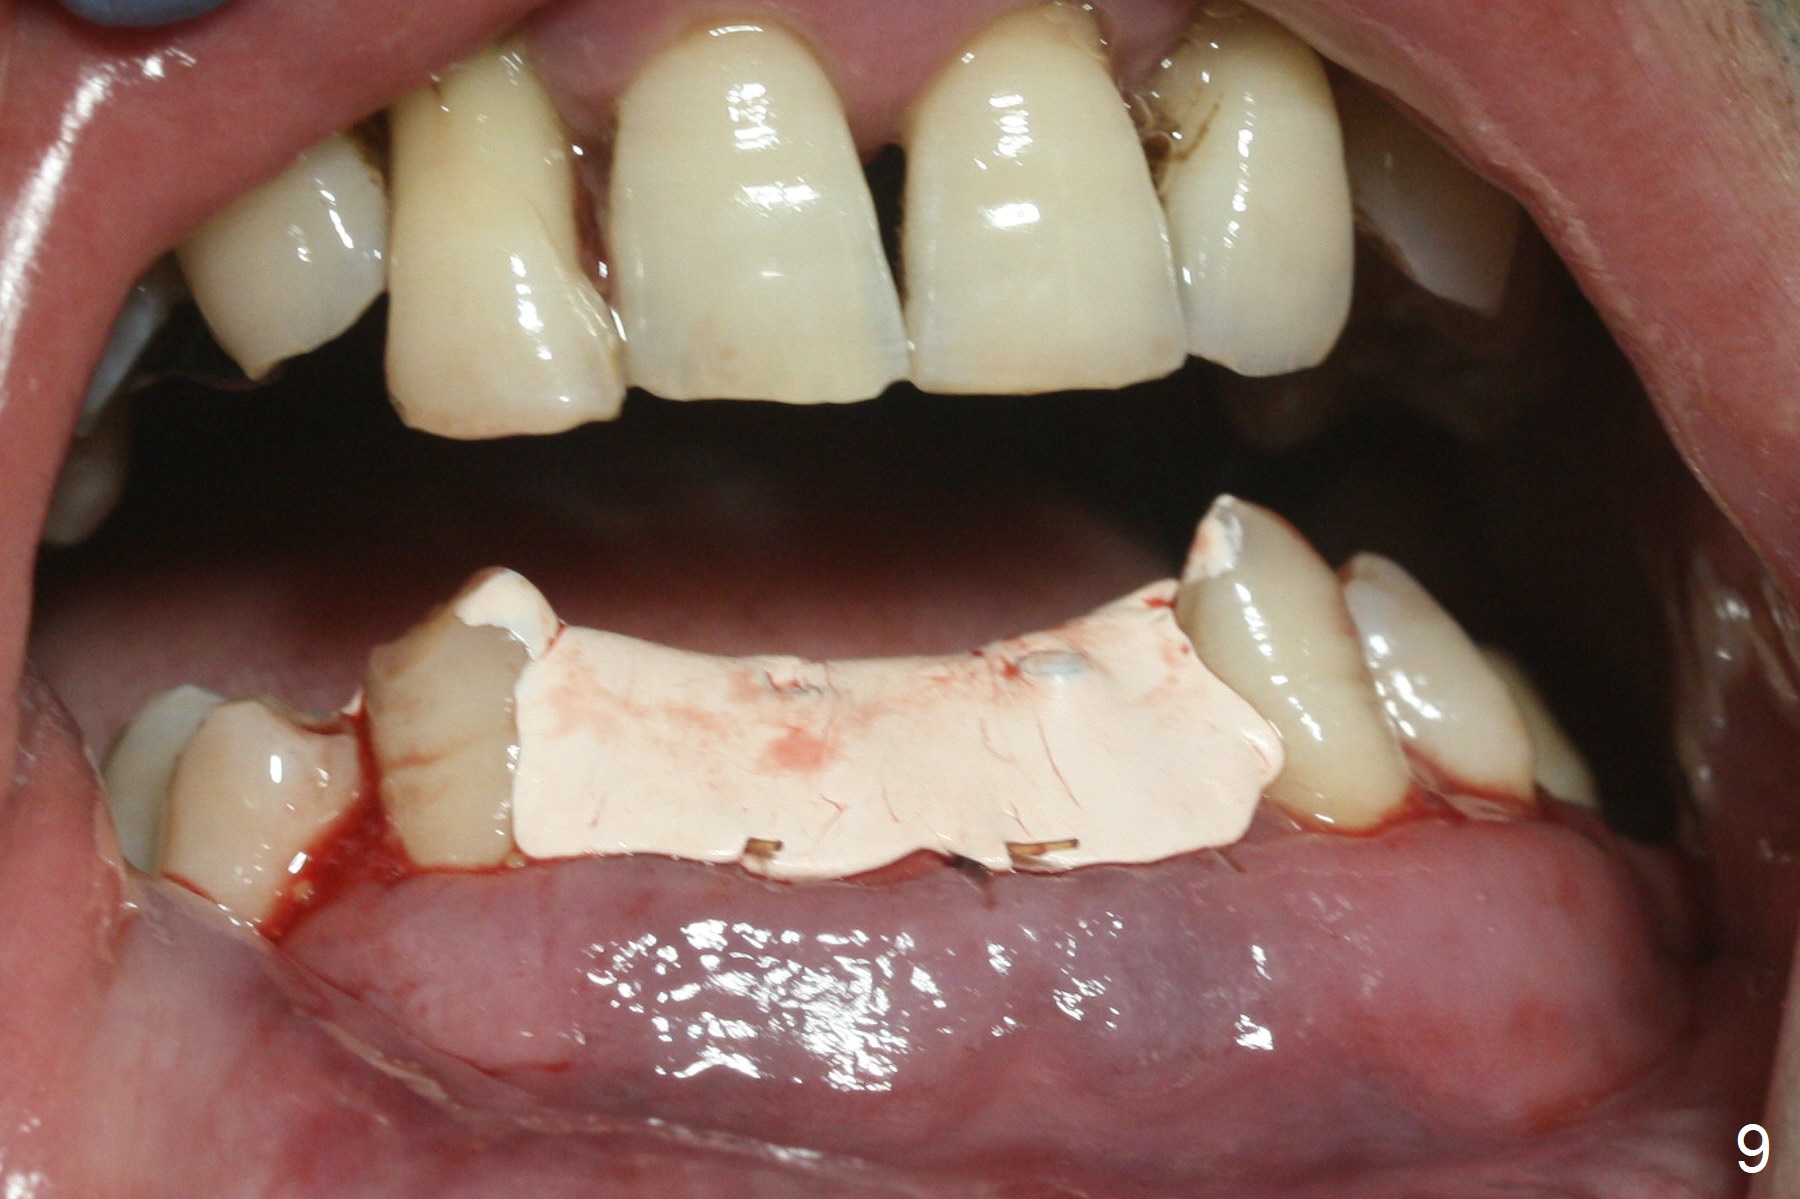

After extraction of 4 of the lower incisors, there are basically 2 sockets (#23/24 and 25/26), separated by the apparently midline bone (Fig.1 red line).  In spite of using Lindamann bur to move the 25/26 osteotomy mesially, a 3x14(2) mm dummy implant remains close to the tooth #27 (Fig.2).  The terminal branch of the Incisive Canal (<) is located between the lateral and central incisors.  A de novo osteotomy (Fig.3 (1.5 mm drill)) is made mesial to the original one (O).  While the 3x14(2) mm dummy implant is incompletely placed at #25/26, a 3x14(4) mm 1-piece one is placed at #23/24 (Fig.4).  Finally the same implant is placed at #25/26 with placement of mineralized cortical/cancellous bone (Fig.5 *).  When the large sockets are sutured, the supraerupted teeth #7-9 touch the lower gingiva (Fig.6).  The incisal edge is reduced for clearance (Fig.7).  Periodontal dressing is less likely to be dislodged with the incisal edge reduction (Fig.8,9).  A provisional FPD is fabricated 1 week postop.  Hard (Fig.10) and soft (Fig.11,12) tissues heal 5.5 months postop.  The patient returns for crown cementation 3 months post impression (9 months postop, Fig.13,14).